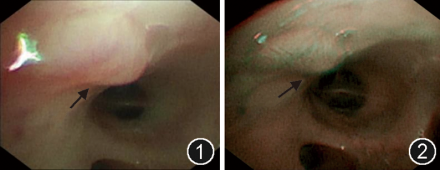

进一步行支气管镜检查,在右下叶基底段开口处见一黏膜下隆起病灶,直径约3 mm,呈缓坡状,表面光滑,无溃疡、糜烂或坏死(图1)。窄带成像(narrow band imaging,NBI)模式下,病灶局部可见迂曲血管影,呈“珊瑚样”改变,提示动脉瘤可能(图2)。考虑到TBDD可能性大,未行活检,以避免致命性大出血。

图1  支气管镜下可见右下叶基底段开口处黏膜下异常隆起病灶,黏膜光滑(箭头示)

图2  支气管镜下可见右下叶基底段开口处病灶,窄带成像(NBI)模式提示动脉瘤可能(箭头示)

TBDD的支气管镜下表现为支气管黏膜下的局部隆起病灶,特征为表面黏膜光滑完整,没有溃疡、糜烂,典型者尖部可有白色透明水肿和坏死(“戴白帽”),周围黏膜正常,无炎症或坏死组织包裹及肿块等其他病灶[2,12, 13, 14]。其病理基础是畸形的支气管动脉没有逐级变细,而是保持恒径进入支气管黏膜下使病变部位的支气管黏膜承压隆起[2,15]。病灶触之易出血。在出血期,可见血管破裂处有喷射状或搏动性出血。位置特点上,病变多位于主支气管或叶段支气管,尤其是气道分叉处,可能与血流动力学因素相关。本文所报道病例,与以上特点相符。